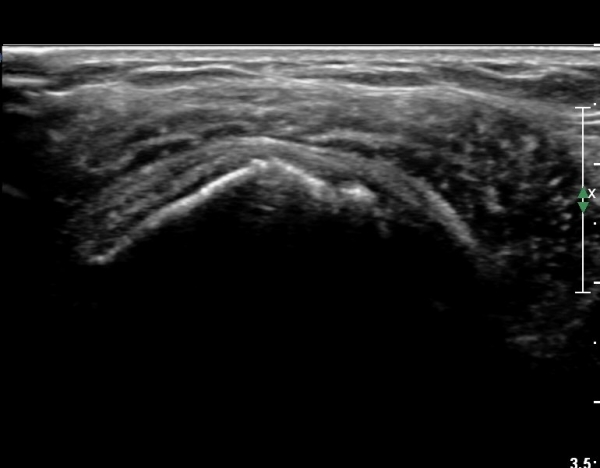

ŽÃËÀÚ¸¦ Á¶±Ý ¾Æ·¡·Î À̵¿ÇÏ¿© À̵ιڱٰÇÀÇ È¾´Ü¸é°Ë»ç¿¡¼­ ÀÌµÎ¹Ú±Ù°Ç ÁÖÀ§ ¼ö¾×Àú·ù°¡ °üÂûµÈ´Ù(»çÁø 3, 4).

À̴ Ȱ¾×¸·¿°Áõ ¼Ò°ßÀ¸·Î Ãæµ¹ÁõÈıº ¶Ç´Â ȸÀü±Ù°³ ÆÄ¿­ ½Ã ÈçÈ÷ °üÂûµÇ´Â

¼Ò°ßÀÌ´Ù.